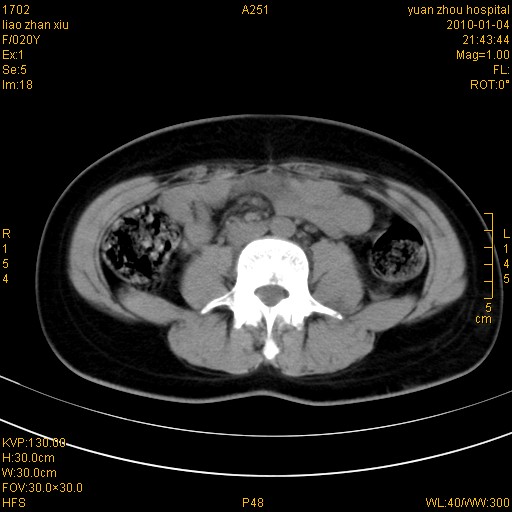

标题: CT23985:F20Y 外伤典型病例

左肾挫伤,包膜下积血。

左肾挫裂伤伴肾被膜下积血!另:肾周筋膜增厚!

1)左肾包膜下血肿。2)左侧肾挫伤可能;建议:行ct增强扫描检查。3)腰椎左侧横突骨折。

左肾挫伤,包膜下积血,l3、4左侧横突多发骨折。

双侧肾胞膜下出血,左侧较多。l3、4左侧横突多发骨折。

1、左肾挫伤,包膜下积血;

2、l3、4左侧横突多发骨折;

3、腹腔积气,考虑肠管破裂?

左肾挫伤,包膜下积血,L1、2、3、4左侧横突多发骨折。